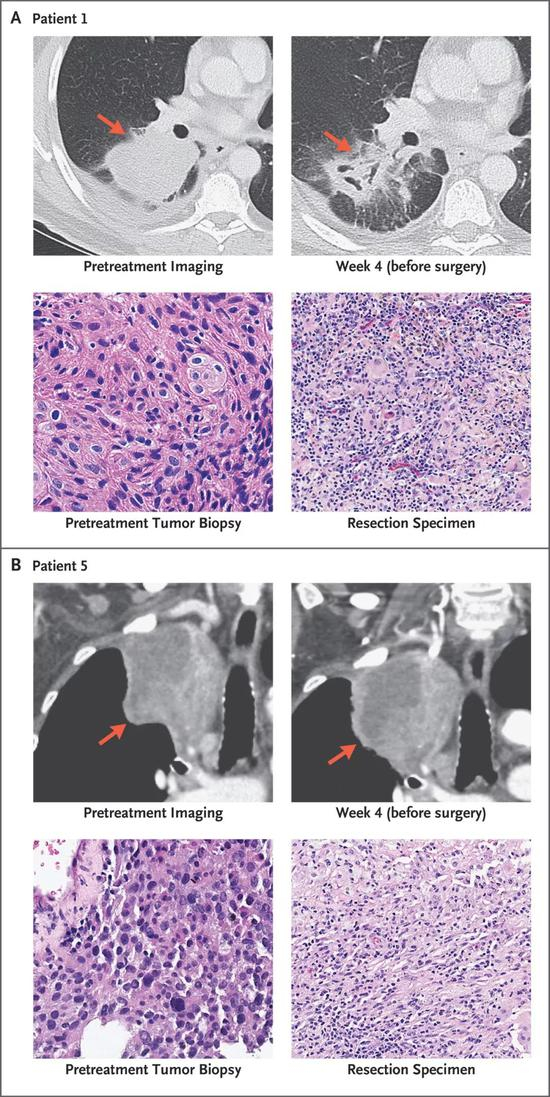

这项试验的主角,是大家再熟悉不过的O药(Nivolumab)。试验总共入组了21名分期在I-IIIA期,可以进行根治手术的肺癌患者,在预定的手术前每两周注射一次O药(3mg/Kg)进行新辅助治疗,两次注射后进行手术。

用研究主导者,约翰·霍普金斯医学院肿瘤免疫治疗研究所主任Drew Pardoll的话说,“我们都被惊呆了”。在手术完全切除肿瘤的20名患者中,9名患者的肿瘤已经实现显著病理学缓解,甚至有两例肿瘤中完全见不到癌细胞!

肉眼可见的改变!

新辅助治疗的安全性也非常好,并没有因为副作用导致手术延期。从手术后的随访来看,20名患者中只出现了3例复发,随访18个月时,患者整体的PFS率是73%,这可比历史数据50%的复发率[9],好看多了。

而手术前使用O药,确实调动了患者体内的T细胞进入抗肿瘤免疫状态,病理切片也证实,大量的T细胞和巨噬细胞浸润到了肿瘤当中。患者的肿瘤突变负荷(TMB),则有望作为预估疗效的生物标记物[10]。